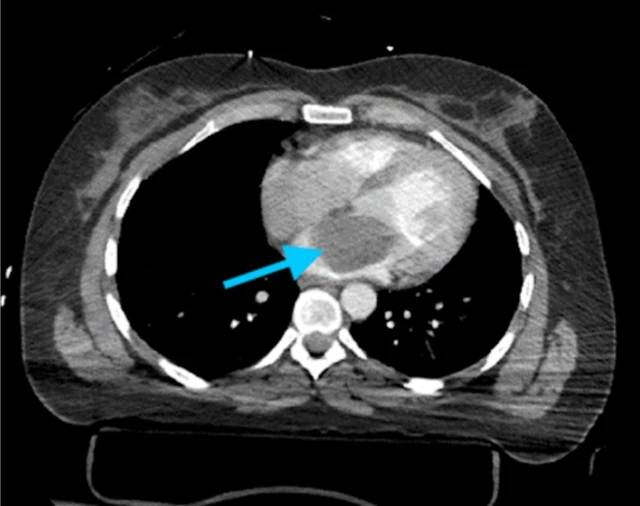

Các khối u tim có kích thước và hình dạng rất đa dạng, từ dưới 1cm đến khoảng 15cm. Kích thước và vị trí của khối u trong tim ảnh hưởng rõ rệt đến các triệu chứng và tiên lượng bệnh. Một số khối u lành tính, dễ điều trị, trong khi một số khác có thể đe dọa tính mạng. Dưới đây là thông tin chi tiết về các khối u tim lành tính và các vấn đề liên quan mà nhà thuốc Long Châu muốn chia sẻ với bạn.

Các khối u ở tim có thể xuất hiện ở bất kỳ mô tim nào. Khối u tim có thể là nguyên phát hoặc di căn. Điều trị các khối u lành tính bằng phẫu thuật cắt bỏ, tuy nhiên khối u có thể tái phát. Điều trị ung thư di căn phụ thuộc vào loại và nguồn gốc khối u, tiên lượng bệnh thường rất xấu.